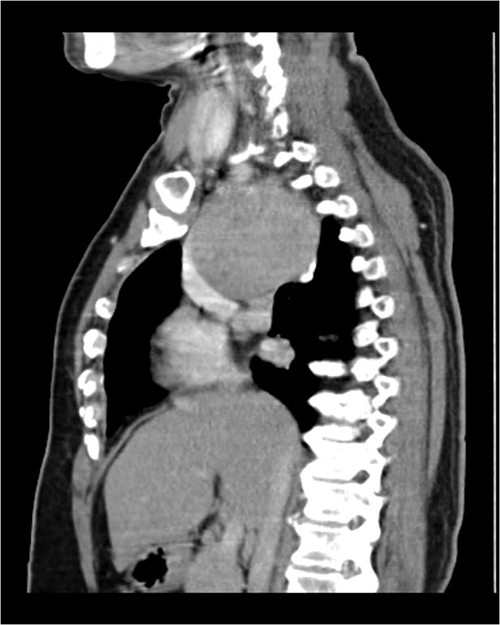

A 57-year-old female came with chest discomfort and cough since 1 month. The chest X-ray (Fig. 1) showed mass in the superior mediastinum. CECT thorax (Fig. 2) revealed the soft tissue density 7 cm × 7 cm (Fig. 3) in superior mediastinum abutting subclavian artery, azygous vein, anteriorly displacing superior venacava, anteromedially abutting arch of aorta, posteromedially compressing trachea and abutting right main bronchus. A 4.9 cm × 5 cm mass in the left side superior mediatinum was seen abutting internal jugular vein and brachiocephalic artery. USG showed the presence of normal thyroid in the neck. CT guided biopsy from the right mass showed ectopic thyroid tissue (ETT)-colloid goiter. Due to close proximity with major vessels sternotomy done. Mass in the left side 5 cm × 5 cm (Fig. 4) in the superior mediastinum was identified, on dissecting superiorly, which was free from the thyroid in the neck and abutting the IJV, brachiocephalic artery and left innominate vein that were separated with meticulous dissection.

CECT scan showing the right side mass displacing superior nn(SVC).

The right mass (Fig. 5) was even bigger and needed an extension of incision into the neck (Fig. 6). About 7 cm × 7 cm noted to be displacing Superior venacava anteriorly that was dissected from it, separated from the first rib and subclavian artery meticulously taking care not to damage any major structure. Both masses were excised. These masses were not connected in any way with each other as well as with the orthotopic thyroid in the neck. Post-op was uneventful. Thyroid functions were normal. Thyroid scan (Fig. 8) showed no evidence of a thyroid tissue in the mediastinum and no other ectopic thyroid was present other than the orthotopic thyroid tissue in neck. The patient was discharged on POD 10 without any symptoms. The histopathological tissue diagnosis showed a colloid goiter (Fig. 7). All data kept in our database.